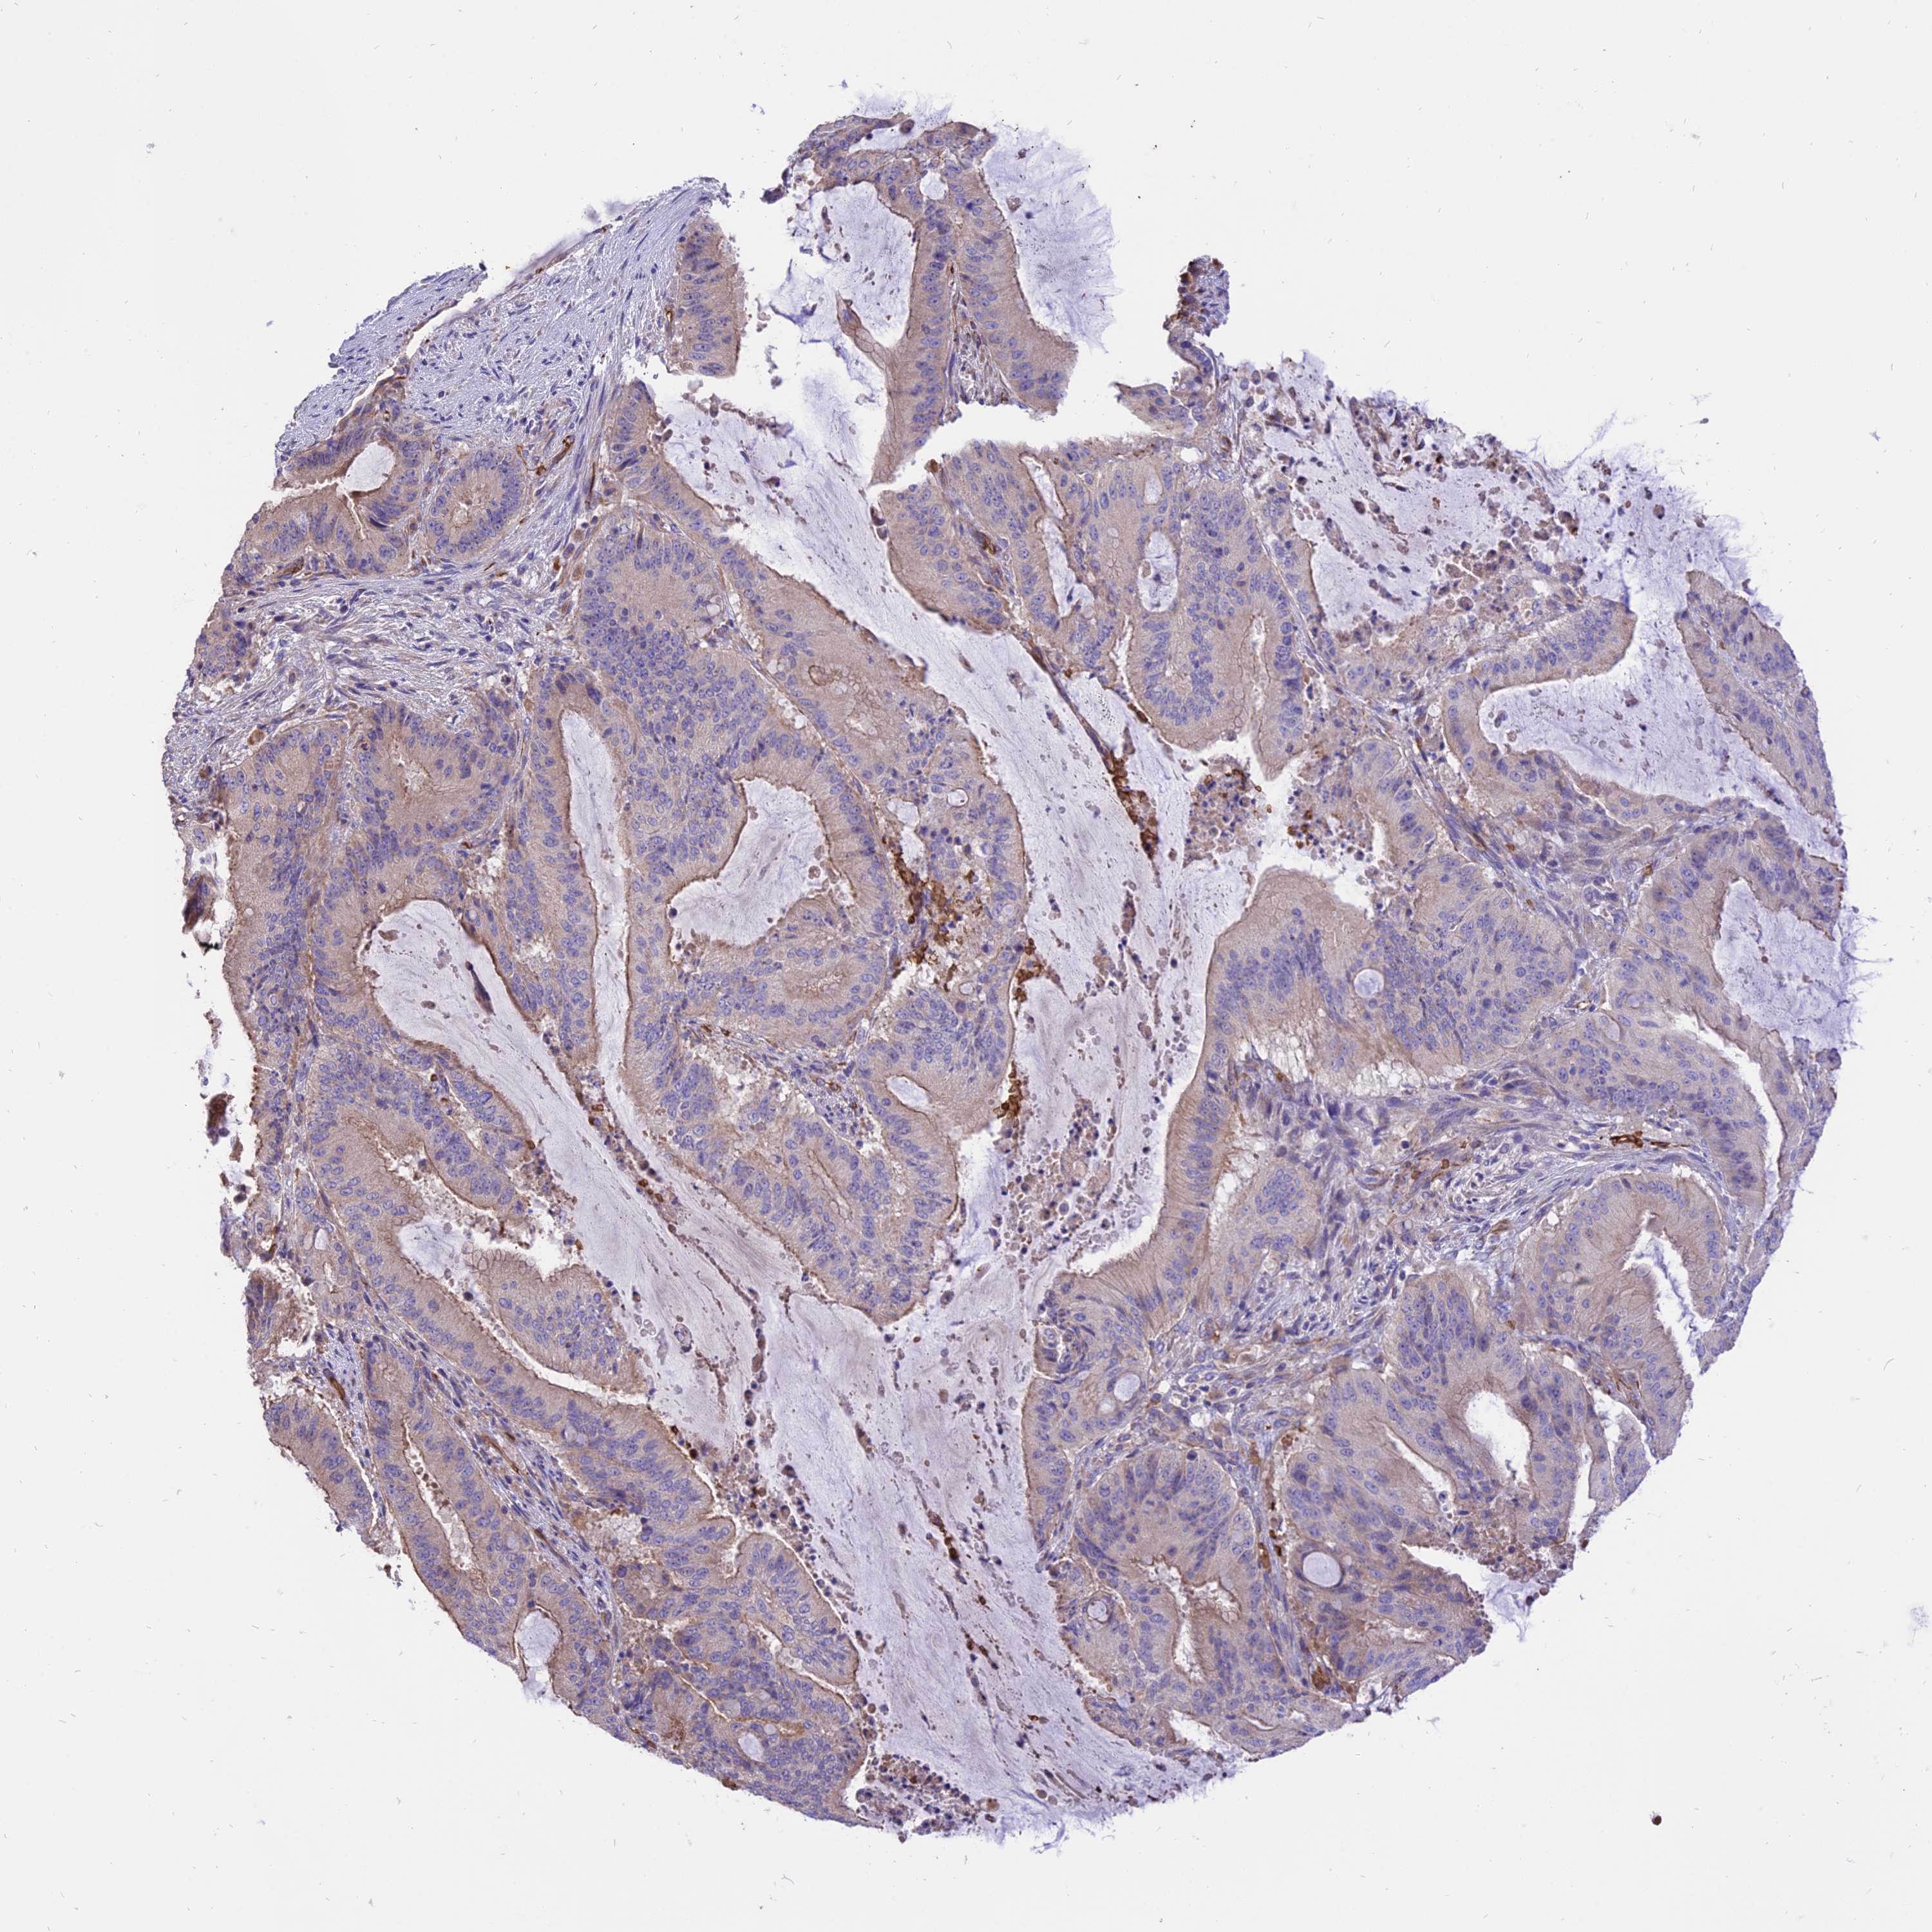

LIVER CANCER - Protein expressioni

A mouse-over function shows sample information and annotation data. Click on an image to view it in a full screen mode. Samples can be filtered based on level of antibody staining by selecting one or several of the following categories: high, medium, low and not detected. The assay and annotation is described here.

Note that samples used for immunohistochemistry by the Human Protein Atlas do not correspond to samples in the TCGA dataset.

Antibody stainingi

Antibody staining in the annotated cell types in the current human tissue is reported as not detected, low, medium, or high, based on conventional immunohistochemistry profiling in selected tissues. This score is based on the combination of the staining intensity and fraction of stained cells.

Each image is clickable and will lead to virtual microscopy that enables deeper exploration of all samples and also displays staining intensity scores, fraction scores and subcellular localization as well as patient and tissue information for each sample.

Antibody HPA041608

Antibody HPA042459

Staining

High

Medium

Low

Not detected

Intensity

Strong

Moderate

Weak

Negative

Quantity

>75%

75%-25%

<25%

None

Location

Nuclear

Cytoplasmic/membranous

Cytoplasmic/membranous,nuclear

Cholangiocarcinoma

Carcinoma, Hepatocellular, NOS